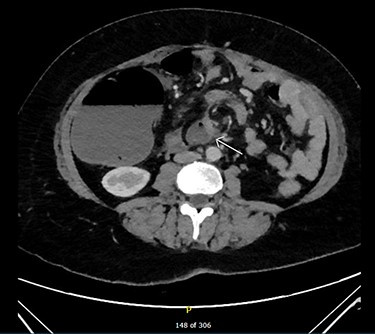

Admission blood tests were unremarkable. Abdominal X-ray showed non-specific signs of large bowel obstruction (Fig. 1). Computed tomography (CT) scan indicated unusual location of the caecum in the right upper quadrant along with gross distension up to 13 cm (Fig. 2), a whirling pattern of mesenteric vessels (Fig. 3) and a competent ileo-caecal valve. In context of her surgical history, these findings raised concern for a closed loop obstruction due to internal herniation.